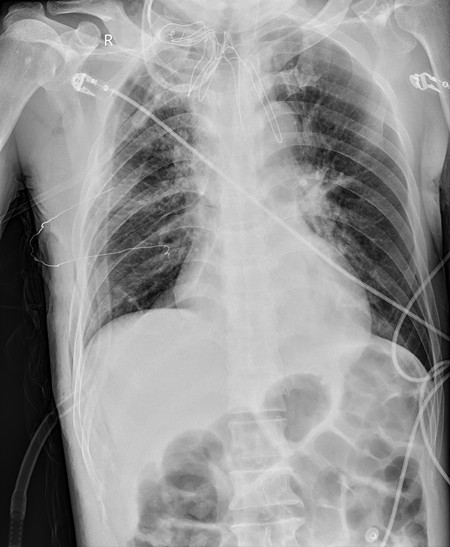

术后胸片

与此前胸外科已完成的ECMO支持下的气管肿瘤切除、隆突重建气管成形术2例,本次手术标志着胸外科气管肿瘤外科治疗水平更上一层楼。